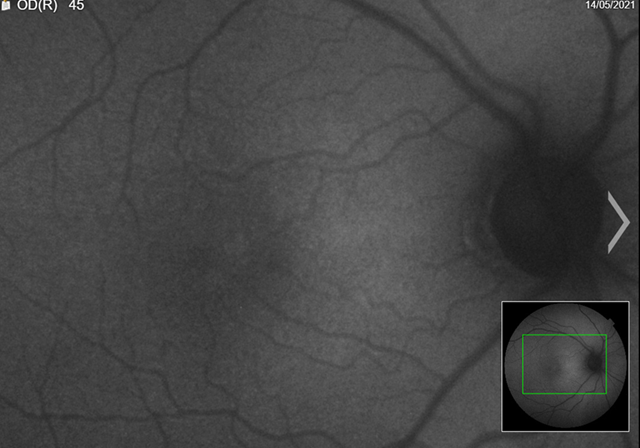

Fundus

autofluorescence (faf) is a non-invasive imaging modality that captures an

image from ocular endogenous fluorophores found within the retinal pigment

epithelium and the choroid. These are composed mainly of lipofuscin and

melanin. By capturing an image composed

of the distribution of lipofuscin and melanin, the clinician can formulate an

impression of the health of the retina/rpe.

The patient’s faf was abnormal. We could see from the images that there were areas of hyper and hypo-autofluorescent spots circumferentially, with the left more defined than right (figures 4a,4b). Magnified images showing defects more clearly (figures 5a,5b).

(a) Right eye

(a)

Left eye

figure 4. Fundus autofluorescence (faf)

(a) Left eye

Figure 5. Fundus autofluorescence (faf) (magnified)